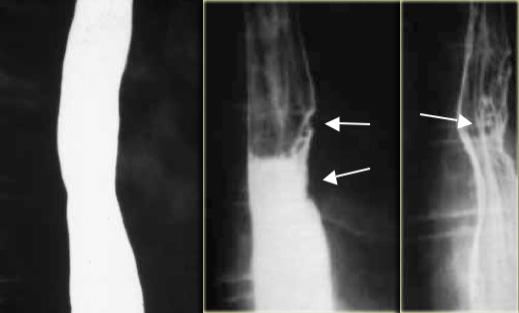

Bên trái là hình ảnh một bệnh nhân bị tụ máu thực quản.

Bệnh nhân nhập viện với triệu chứng đau ngực và khó nuốt sau khi nôn mửa.

Ngoài hình ảnh động mạch chủ ngoằn ngoèo, X-quang ngực bình thường.

Chụp thực quản barium cho thấy lòng thực quản hẹp (các mũi tên) trên phim thẳng và lòng thực quản dẹt trên phim nghiêng (các đầu mũi tên), gợi ý tụ máu trong thành thực quản.

Trên CT, chẩn đoán tụ máu trong thành thực quản được xác nhận.

Khối tụ máu thành thực quản tăng tỷ trọng (đầu mũi tên) được thấy cạnh ống thông mũi – dạ dày (mũi tên).

Sau điều trị bảo tồn, sáu tháng sau chụp thực quản barium cho kết quả bình thường.

Bên trái là hình ảnh một bệnh nhân có biến chứng sau nội soi phức tạp.

Can thiệp dụng cụ gây rách niêm mạc và tụ máu trong thành thực quản dạng bóc tách, tạo ra hình ảnh lòng đôi với dải niêm mạc phân tách (các mũi tên).

Ngoài cùng bên trái là hình ảnh thoát thuốc cản quang trong thành thực quản (mũi tên) sau nong đoạn xa điều trị co thắt tâm vị.

Ở giữa là hình ảnh thoát thuốc cản quang trong thành thực quản (mũi tên) sau nội soi phức tạp.

Bên phải là hình ảnh thủng thực quản sau sinh thiết với thuốc cản quang thoát ra ngoài lòng thực quản (mũi tên).